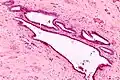

High magnification micrograph of endosalpingiosis, showing the characteristic cystic spaces lined by a simple epithelium with cilia. H&E stain.

It is characterized by cysts with tubal-type epithelium (e.g. ciliated epithelium) surrounded by a fibrous stroma. It is not often associated with hemorrhage.